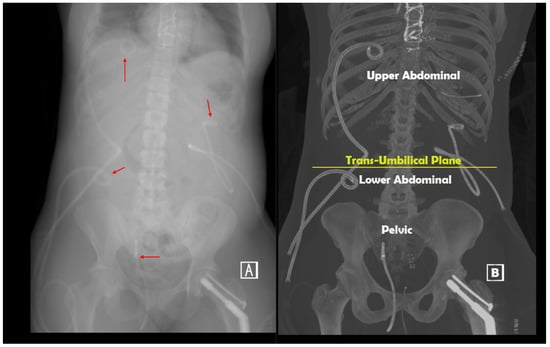

2. Materials and Methods

| Intra-Abdominal Pressure Increases by Region | |||

|---|---|---|---|

| Standardized Pull (1500 cc) | Max Pull (Average 1999 cc) | ||

| Upper Abdomen | Upper Abdomen | ||

| Mean ± STD | 61.6 ± 54.2 | Mean ± STD | 82.5 ± 54.8 |

| Median | 54.4 | Median | 54.4 |

| Min-Max | 18.1–154 | Min-Max | 27.2–154 |

| Lower Abdomen | Lower Abdomen | ||

| Mean ± STD | 42.3 ± 18.9 | Mean ± STD | 39.3 ± 13.8 |

| Median | 36.2 | Median | 36.2 |

| Min-Max | 27.2–63.4 | Min-Max | 27.2–54.4 |

| Pelvis | Pelvis | ||

| Mean ± STD | 48.7 ± 35.9 | Mean ± STD | 54.4 ± 35.3 |

| Median | 40.8 | Median | 43.1 |

| Min-Max | 27.2–136 | Min-Max | 22.7–136 |